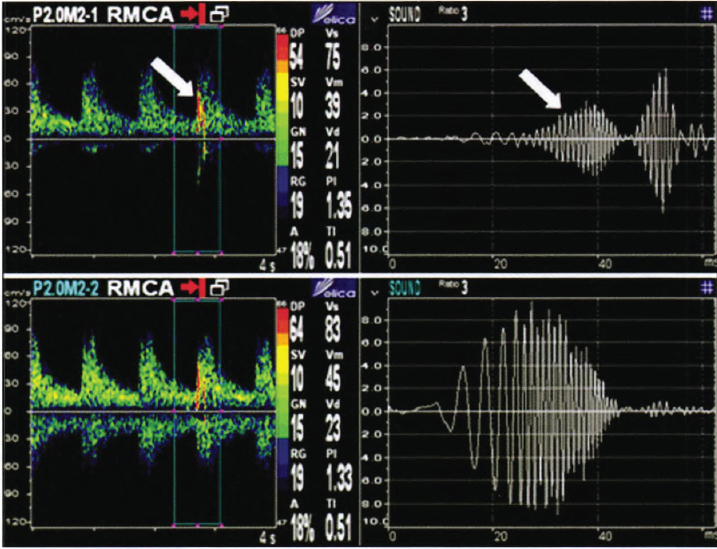

經(jīng)顱多普勒監(jiān)測MES聲譜圖

經(jīng)顱多普勒微栓子監(jiān)測93例腦梗死患者分析報(bào)告

目的探討微栓子信號(hào)(MES)與腦梗死不同亞型及卒中危險(xiǎn)因素的關(guān)系,并對(duì)影響MES監(jiān)測陽性率的相關(guān)因素進(jìn)行分析。

方法對(duì)93例缺血性腦卒中患者行MES監(jiān)測,據(jù)監(jiān)測結(jié)果分為MES陽性組與陰性組。收集患者臨床信息,依據(jù)TOAST分型標(biāo)準(zhǔn)進(jìn)行腦梗死亞型分組。應(yīng)用SPSS 17.0統(tǒng)計(jì)軟件進(jìn)行數(shù)據(jù)分析。

結(jié)果MES陽性共9例(9.68%),其中大動(dòng)脈粥樣硬化型(LAA)7例、小動(dòng)脈閉塞型(SAO)1例、心源性栓塞型(CE)1例,所占比例分別為77.8%、11.1%、11.1%。在LAA型中MES陽性率為15.5%,SAO型及CE型中MES陽性率分別為3.8%、5.3%,組間比較無明顯統(tǒng)計(jì)學(xué)差異。MES陽性組與陰性組在血糖[(7.69±3.46)mmol/L VS(5.89士2.34)mmol/L,P一0.040]及尿酸水平[(227.07±57.71)ttmol/L VS(306.47±103.59)扯mol/L,P一0.027],存在明顯差異。MES監(jiān)測距起病時(shí)間平均(4.89±3.39)d,距用藥時(shí)間平均(3.03±2.28)d。

結(jié)論MES陽性常見于LAA型腦梗死患者,SAO型少見。MES陽性率受卒中起病時(shí)間及藥物治療影響。